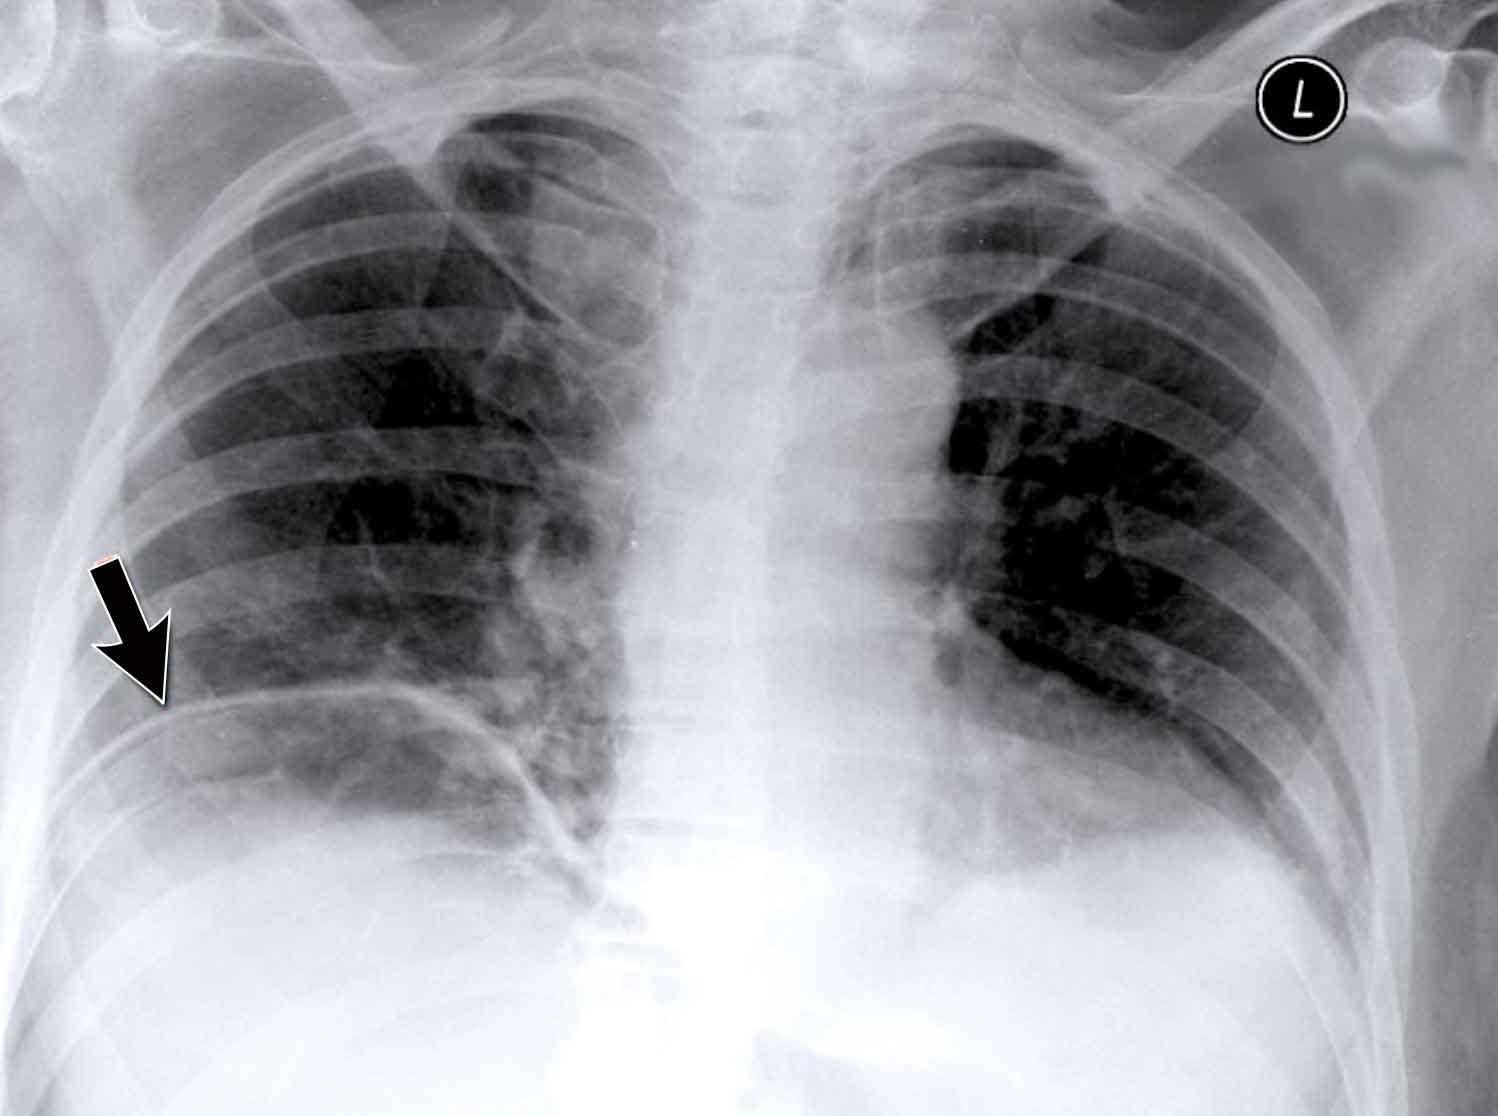

Hidden Areas (2): Right Lower Lobe Lesion

This example demonstrates a large mass in the right lower lobe that is challenging to identify on the PA view unless close attention is paid to the hidden areas.

• On initial inspection, the lesion is inconspicuous.

• However, with focused review of the subdiaphragmatic and retrocardiac regions, the abnormality becomes evident.

• Enlarge the image for better visualization.

Hidden Areas (3): Pneumonia Below the Diaphragm

In this case, a pneumonia was primarily located below the right diaphragmatic dome (yellow arrow), within the posterior basal segment of the right lower lobe.

• On the lateral view, there is an increase in opacity over the lower thoracic vertebrae, indicating lower lobe consolidation (arrow).

• Again, image magnification may be necessary for adequate assessment.